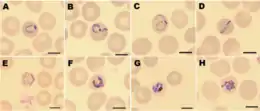

| Giemsa-stained smears of Plasmodium knowlesi infecting human red blood cells | |

Malaria is traditionally diagnosed by examining Giemsa-stained blood films under a microscope; however, differentiating P. knowlesi from other Plasmodium species in this way is challenging due to their similar appearance.[11] P. knowlesi ring-stage parasites stained with Giemsa resemble P. falciparum ring stages, appearing as a circle with one or two dark dots of chromatin.[17] Older trophozoites appear more dispersed, forming a rectangular-shape spread across the host cell called a "band-form" that resembles the similar stage in P. malariae.[17] During this stage, dots sometimes appear across the host red blood cell, called "Sinton and Mulligans' stippling".[17] Schizonts appear, similarly to other Plasmodium species, as clusters of purple merozoites surrounding a central dark-colored pigment.[17]